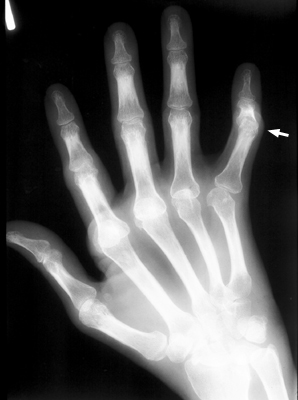

Among the many osseous abnormalities that may be seen in Rheumatoid Arthritis, the boutonniere deformity is the culmination of multiple abnormalities in the hand. Specifically, the deformity arises from hyperextension of the distal interphalangeal joint, while the proximal interphalangeal joint is flexed.